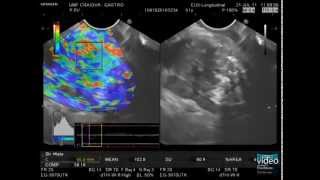

EUS FNA of a pancreatic tumor with wet suction technique - EndoClubNord 2018 Pancreatic Cancer -- Advanced EUS Imaging: Real-Time EUS Elastography

Pancreatic Cancer -- Advanced EUS Imaging: Real-Time EUS Elastography What is EUS/FNA? How does this help with pancreatic cancer treatment? (Kulwinder Dua, MD)